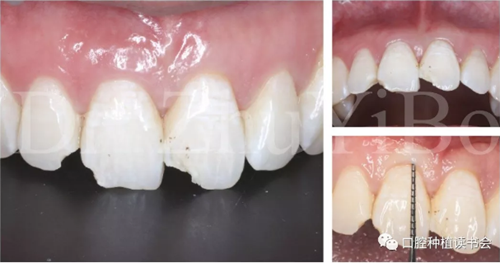

臨床檢查發(fā)現(xiàn):右上中切牙冠根折,斷面位于齦緣下4到5個(gè)毫米。左上中切牙及右上側(cè)切牙,切角缺損,牙髓活力正常(圖7)。

術(shù)前cbct顯示:右上中切牙牙根牙槽突類(lèi)型為一型(圖8)。牙齦為厚型牙齦類(lèi)型;咬合關(guān)系基本正常。

圖7 外傷導(dǎo)致11冠根折